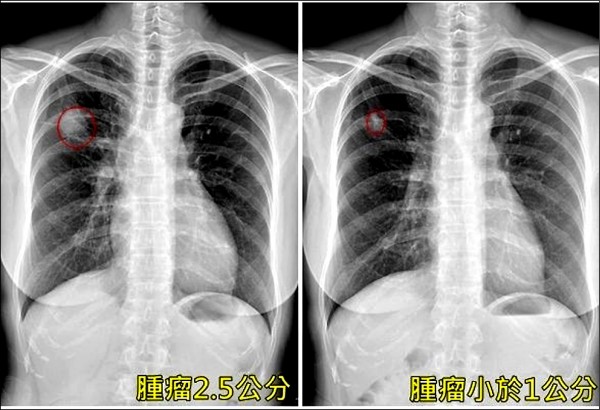

圖片來源:民視

圖片來源:自由時報